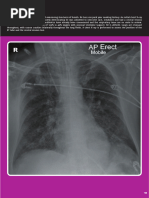

Main Features

Erect PA chest Xray is preferred

1. Cardiomegaly

2. Redistribution-

3. Interstitial edema-

4. Pleural effusion-

5. Alveolar edema-

Cardiomegaly

Cardiothoracic ratio>0.5 in

PA view)

Redistribution of

Pulmonary blood

flow

● Cephalisation (upper

lobe diversions)

● Increased artery to

bronchus ratio

Interstitial edema

● Kerley B lines-fluid in

interlobular septum at

borders of chest

● Peribronchial cuffing

● Thickened lung fissures

Pleural effusion,

Alveolar edema

● Pleural effusion- loss of

costophrenic /

cardiophrenic angles,

meniscus sign

● Alveolar edema- batwing

appearance